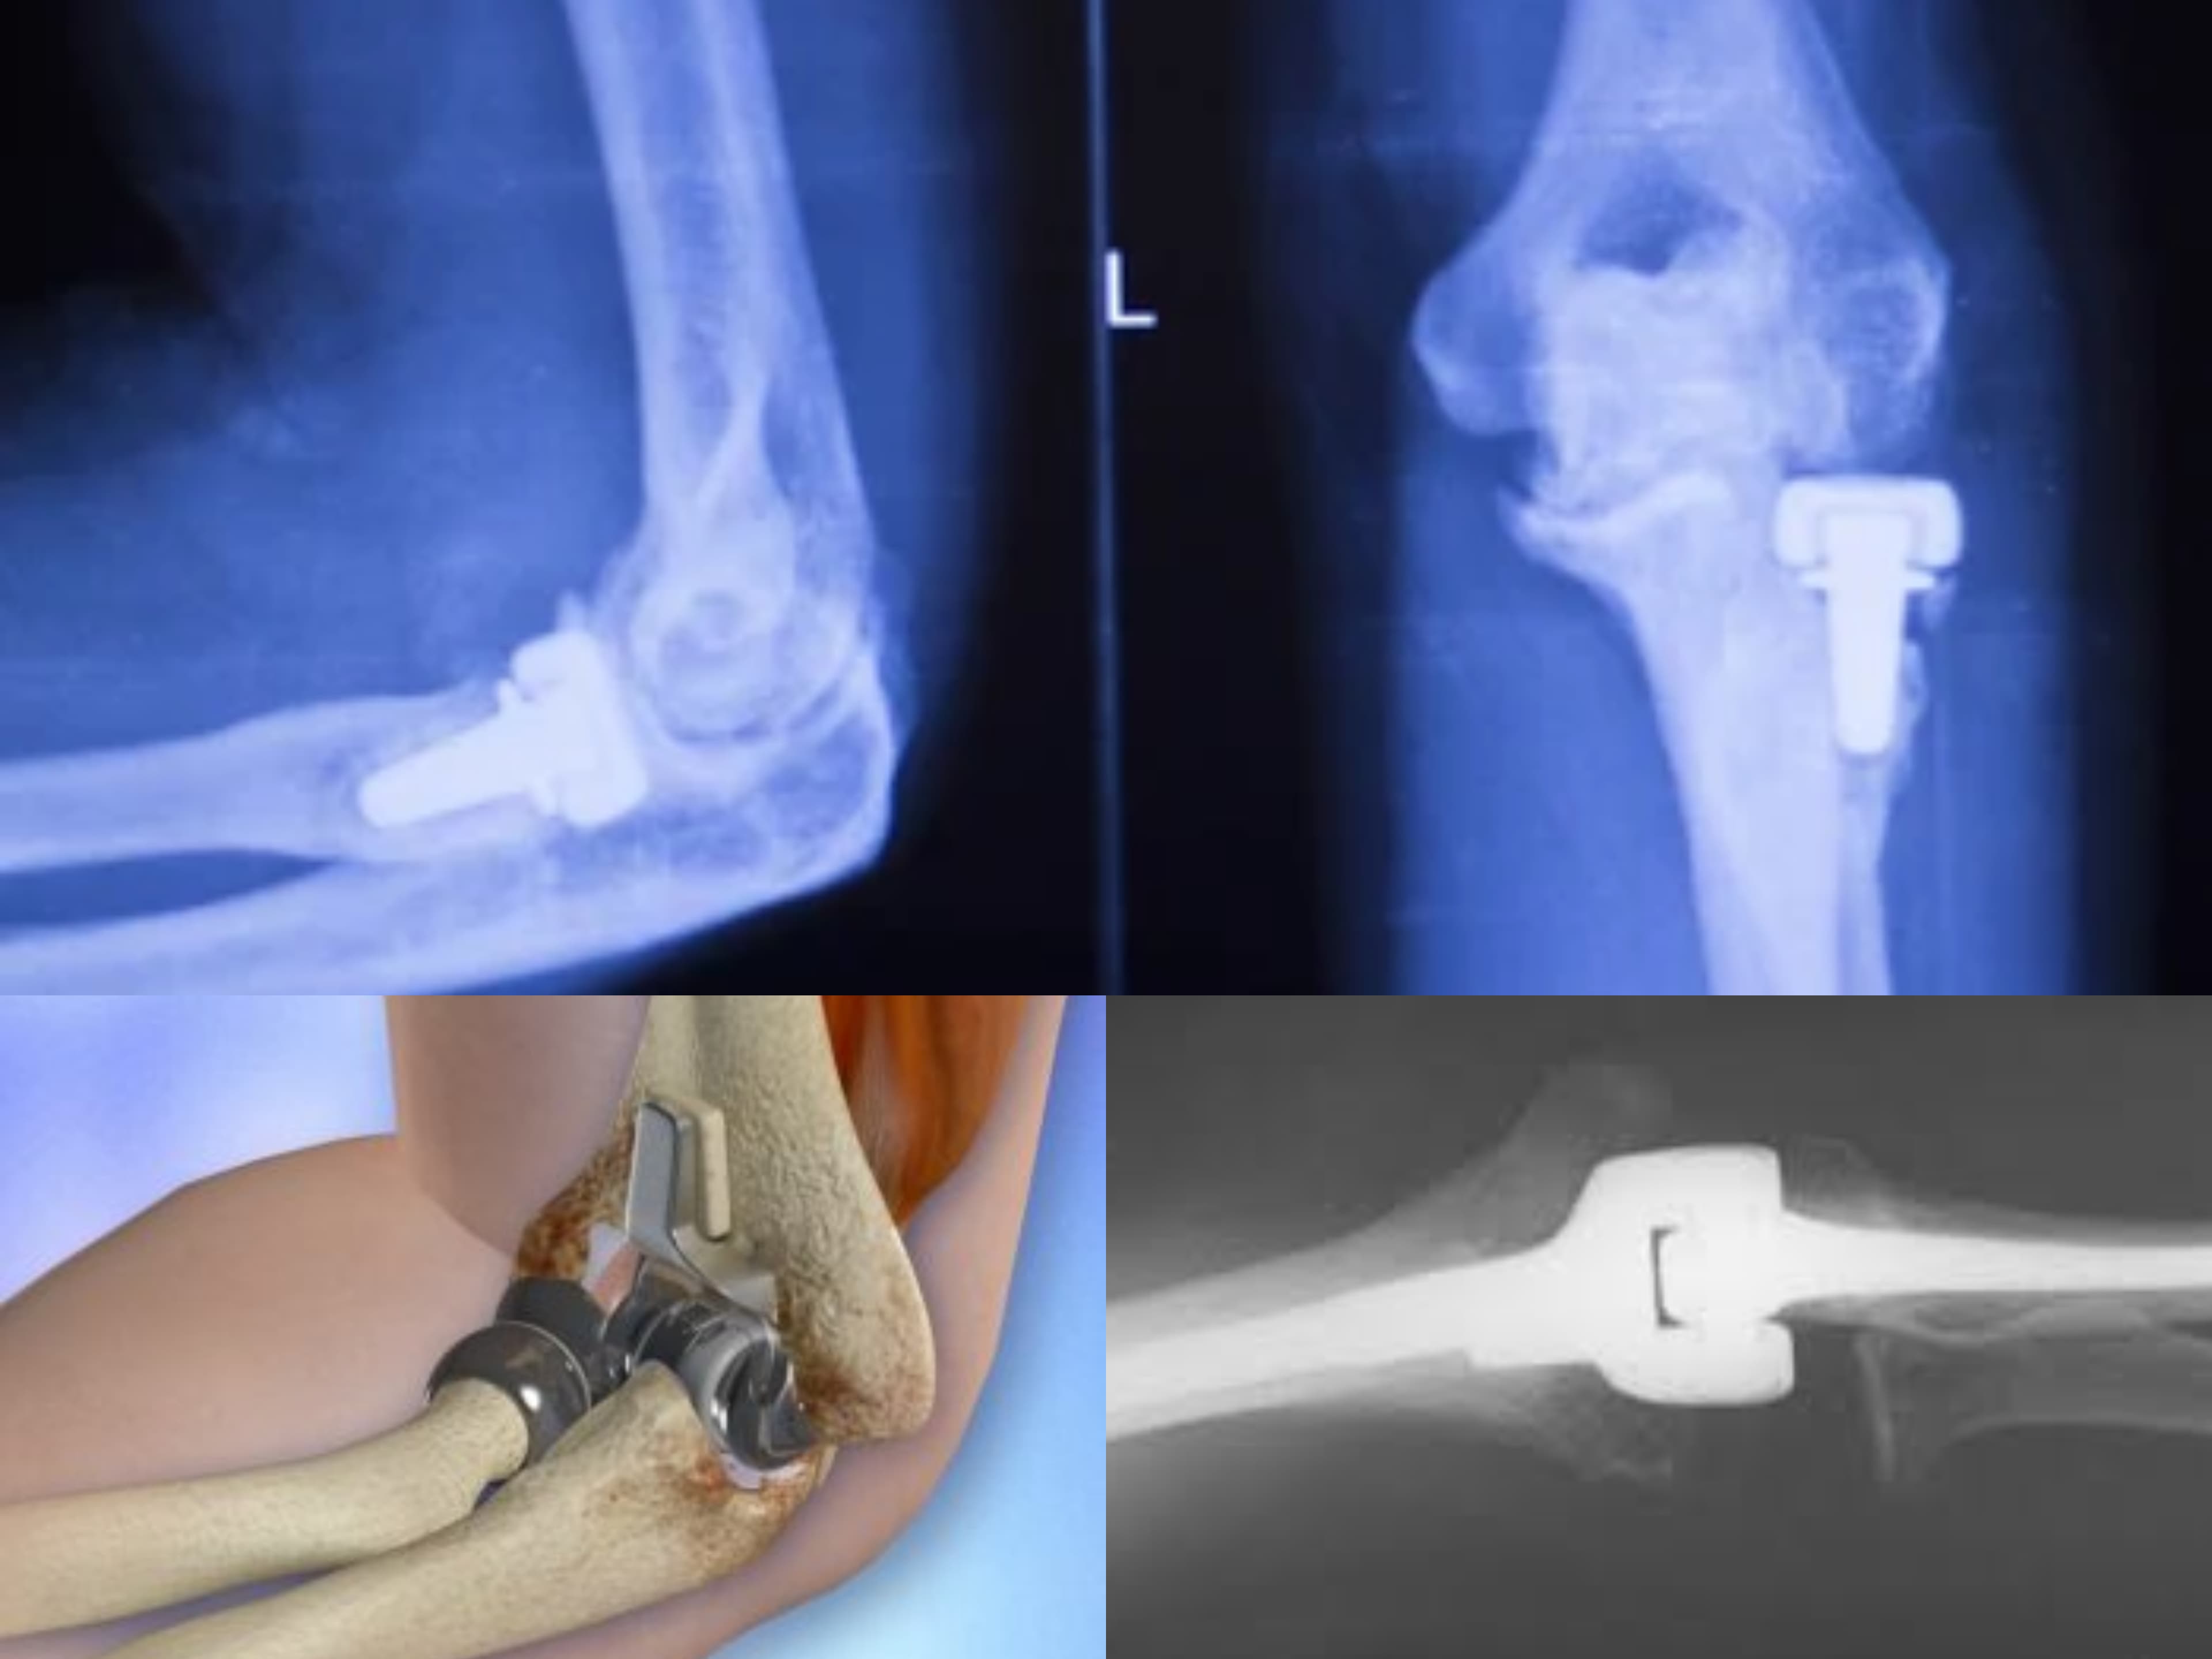

Many users have shared their positive experiences of successful surgeries, such as ACL keyhole surgery, hip replacement, and knee replacement surgeries. The staff is helpful and courteous in assisting patients with formalities and appointments.